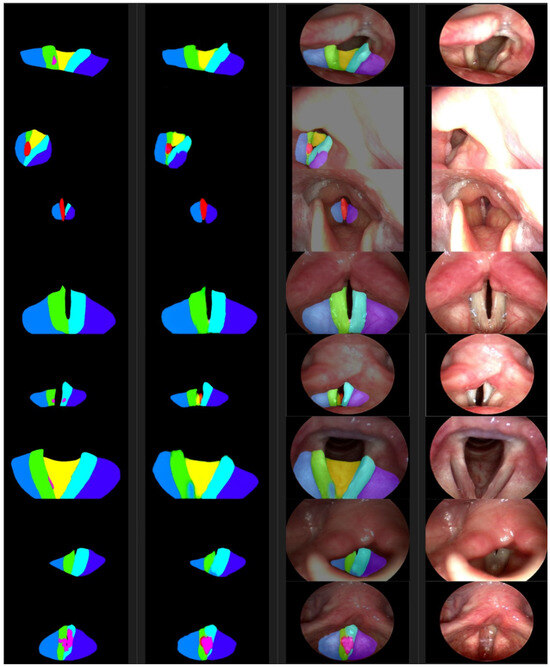

Figure 5. From the left are the ground truth examples, segmentations, photosyntheses, and photographic images. The color of a segmented area represents the class as defined in Table 1.